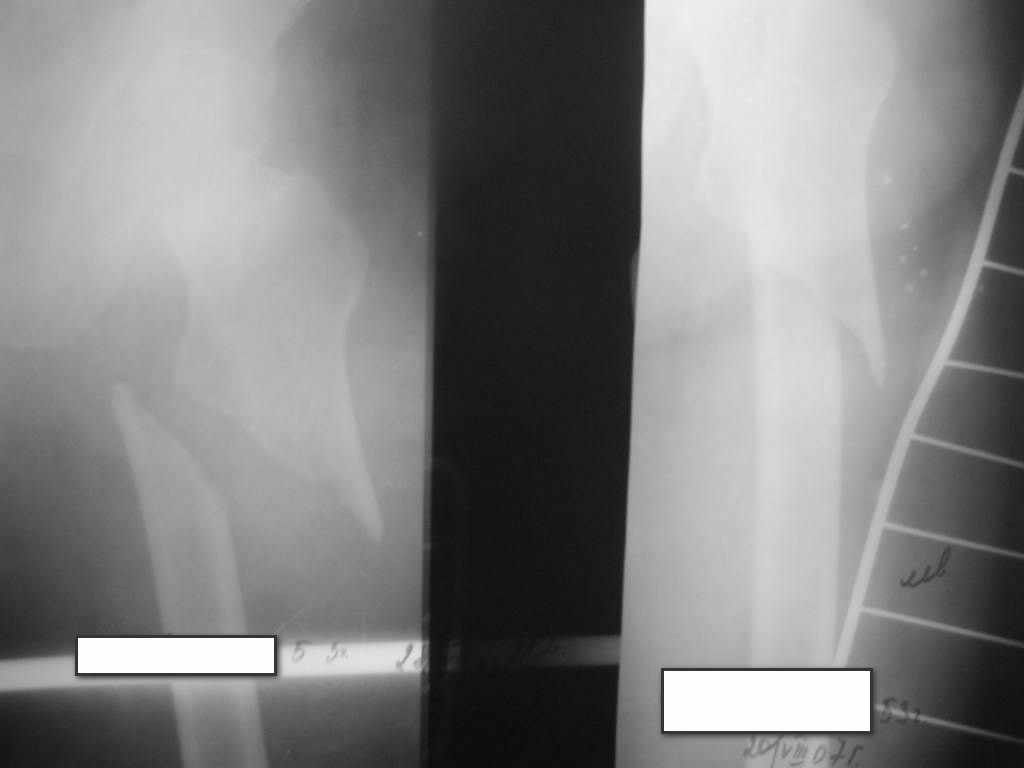

Здравствуйте коллеги! Больная после дорожной аварии. Женщина 53 года .

Диагноз :ЗЧМТ Ушиб головного мозга легкой степени. Подвертельный перелом левого бедра. Подголовчатый перелом шейки левого бедра . В РАО 5 дней переведена в отделение.

Спасибо за уделенное внимание. (P.S извините за качество снимков)

Если и вводить, хватит одного. Непонятно, ужна ли репозиция шейки. Обычно при переломах диафиза перелом шейки вертикальный, от среза. Здесь как-о непонятно, что за геометрия, как смещены отломки.

По этим снимкам что-то планировать нельзя. Надо бы добиться снимков приемлемого качества.

Привет. Сустав не видно (будем считать, что без артроза). Подголовчатый = субкапитальный но благостный (Гарден 1 , Паувелс 1). А посему =